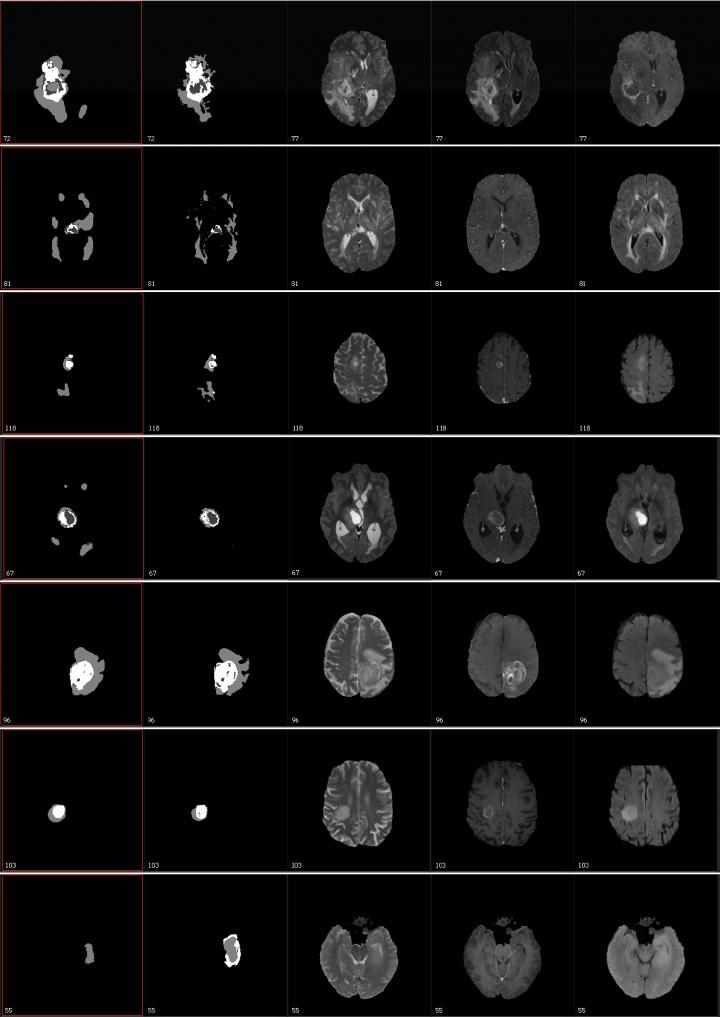

"The competition is related to the characterization of abnormal tissue on patients who suffer from glioma tumors, the most prevalent form of primary brain tumor," Biros said. "Our goal is to take an image and delineate it automatically and identify different types of abnormal tissue - edema, enhancing tumor (areas with very aggressive tumors), and necrotic tissue. It's similar to taking a picture of one's family and doing facial recognition to identify each member, but here you do tissue recognition, and all this has to be done automatically."

The image processing, analysis and prediction pipeline that Biros and his team used has two main steps: a supervised machine learning step where the computer creates a probability map for the target classes ("whole tumor," "edema," "tumor core"); and a second step where they combine these probabilities with a biophysical model that represents how tumors grow in mathematical terms, which imposes limits on the analyses and helps find correlations.